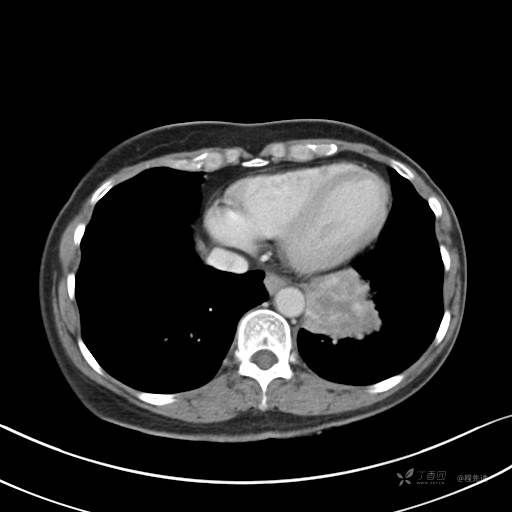

增强动脉期

动脉期CT值约74HU